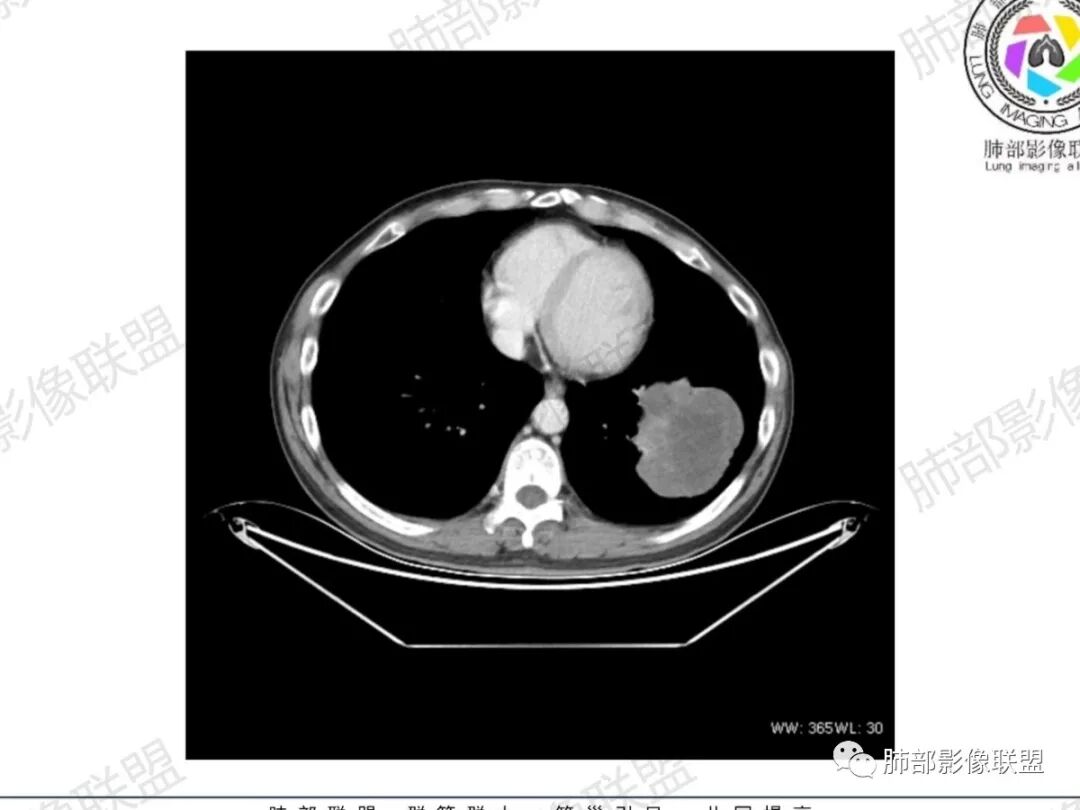

一切∮随缘:左肺下叶类圆形肿块,边缘光滑,彭隆,分叶,脐凹征,病灶近段似支气管堵塞,远端可见阻塞性肺炎,胸膜下结节与肿块相连,平扫密度欠均匀,增强后不均匀强化,男性54岁,炎症指标正常,考虑恶性,肉瘤样癌,鳞癌,肉瘤(滑膜肉瘤,纤维肉瘤)

王秀仙:左肺下叶肿块,边缘光滑、膨隆,分叶状,大片坏死,近侧沿着支气管侵犯,远侧阻塞性肺炎,实性部分明显不均匀强化。考虑肉瘤样癌,鉴别鳞癌。

宇宙:左肺下叶巨大肿块,深分叶,无明显毛刺,支气管截断,近侧沿支气管生长,呈烧瓶状,胸膜侧阻塞炎症,不均匀强化,坏死明显,左下肺门轻度增大淋巴结,考虑肺癌,鳞癌?肉瘤样癌?大细胞癌?

采莲:中年男性,咳嗽咯血,左肺下叶巨大类圆形肿块,边缘膨隆,深分叶,支气管受压推移,不均匀强化,内有大片多灶坏死,考虑肺肉瘤或肉瘤样癌,鉴别大细胞肺癌。

小兜:男性,54岁,咳嗽咳痰血入院。CT示左肺下叶占位,分叶,边缘光滑,远端胸膜下可见阻塞性炎症,增强扫描实性成分不均匀强化,内部可见多发坏死区,边界不清。综合考虑为恶性,鳞癌,肉瘤样癌

流心明智:男,54,咳嗽、痰血入院。胸CT:左肺下叶类圆形肿块,边缘光滑、膨隆、分叶,支气管截断,滋养血管,病灶近段似支气管堵塞,远端阻塞性肺炎,胸膜下结节与肿块相连,增强后不均匀强化,斑片状模糊低密度区。考虑恶性,肉瘤样癌?鳞癌?鉴别隔离等。

一米阳光:中年男性,左肺下叶肿块,分叶,土豆样,周围磨玻璃影;内见大片状低密度坏死,增强实性部分明显强化,坏死实变边缘较清楚。考虑恶性,肉瘤样癌,鉴别鳞癌。

心灵鸡汤:中老年男性,咳血就诊,左肺下叶团状软组织影,密度不均,边界清,边缘膨隆,有深分叶,远侧有斑片模糊影,增强不均匀强化,内见不强化低密度区,病灶内肺血管边界显示模糊,定位肺内,常规考虑恶性肿瘤,肉瘤?鳞癌?其他?建议穿刺活检。